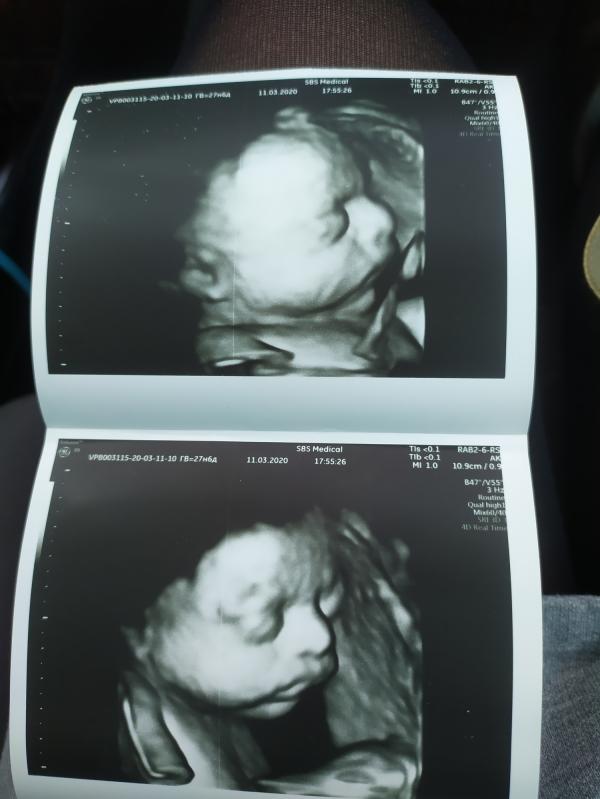

Сегодня делали 4д узи)

Как быстро летит время)

В очередной раз убедилась что когда ты идёшь платно тебе все нормально расскажут,покажут, объяснят.